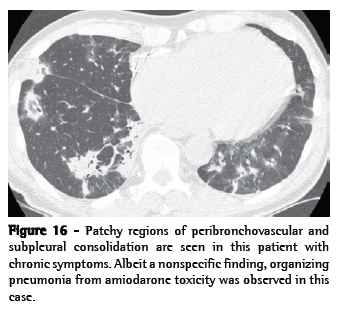

Pattern 3. Increased lung opacity

Increased lung opacity can be described as ground-glass opacity or consolidation. Ground-glass opacity (Figure 15) is increased lung opacity that does not obscure the associated vessels and represents abnormalities below the resolution of HRCT. Consolidation (Figure 16) is increased lung opacity in which the vessels are obscured and represents confluent disease. These findings are quite nonspecific and can reflect diseases that are primarily alveolar, interstitial, or mixed. The differential diagnosis of ground-glass opacity and consolidation overlaps greatly and is predominantly based upon symptom duration: acute or chronic (Chart 8). The distribution of findings (focal, patchy, or diffuse/symmetric) can be helpful in further narrowing the differential diagnosis (Chart 9).

Chronic forms of organizing pneumonia

Chronic smoldering forms of noninfectious OP can produce clinical findings of progressive dyspnea, low fever, constitutional symptoms, and lung consolidations that are unresponsive to the standard treatment for infectious pneumonia. Many conditions can result in OP. In a study conducted in the city of São Paulo, Brazil and involving 95 patients, OP was idiopathic in one third of the cases and secondary to an identifiable cause in of the remaining cases.(90) The most common causes were: drugs (especially amiodarone and MTX), environmental exposure (such as that seen in HP), chronic aspiration, and CTD. Consolidations, central or peripheral, were seen in 64% of cases, ground-glass opacity in 53%, and nodules in 26%. Transbronchial biopsy was diagnostic in 58% of cases.